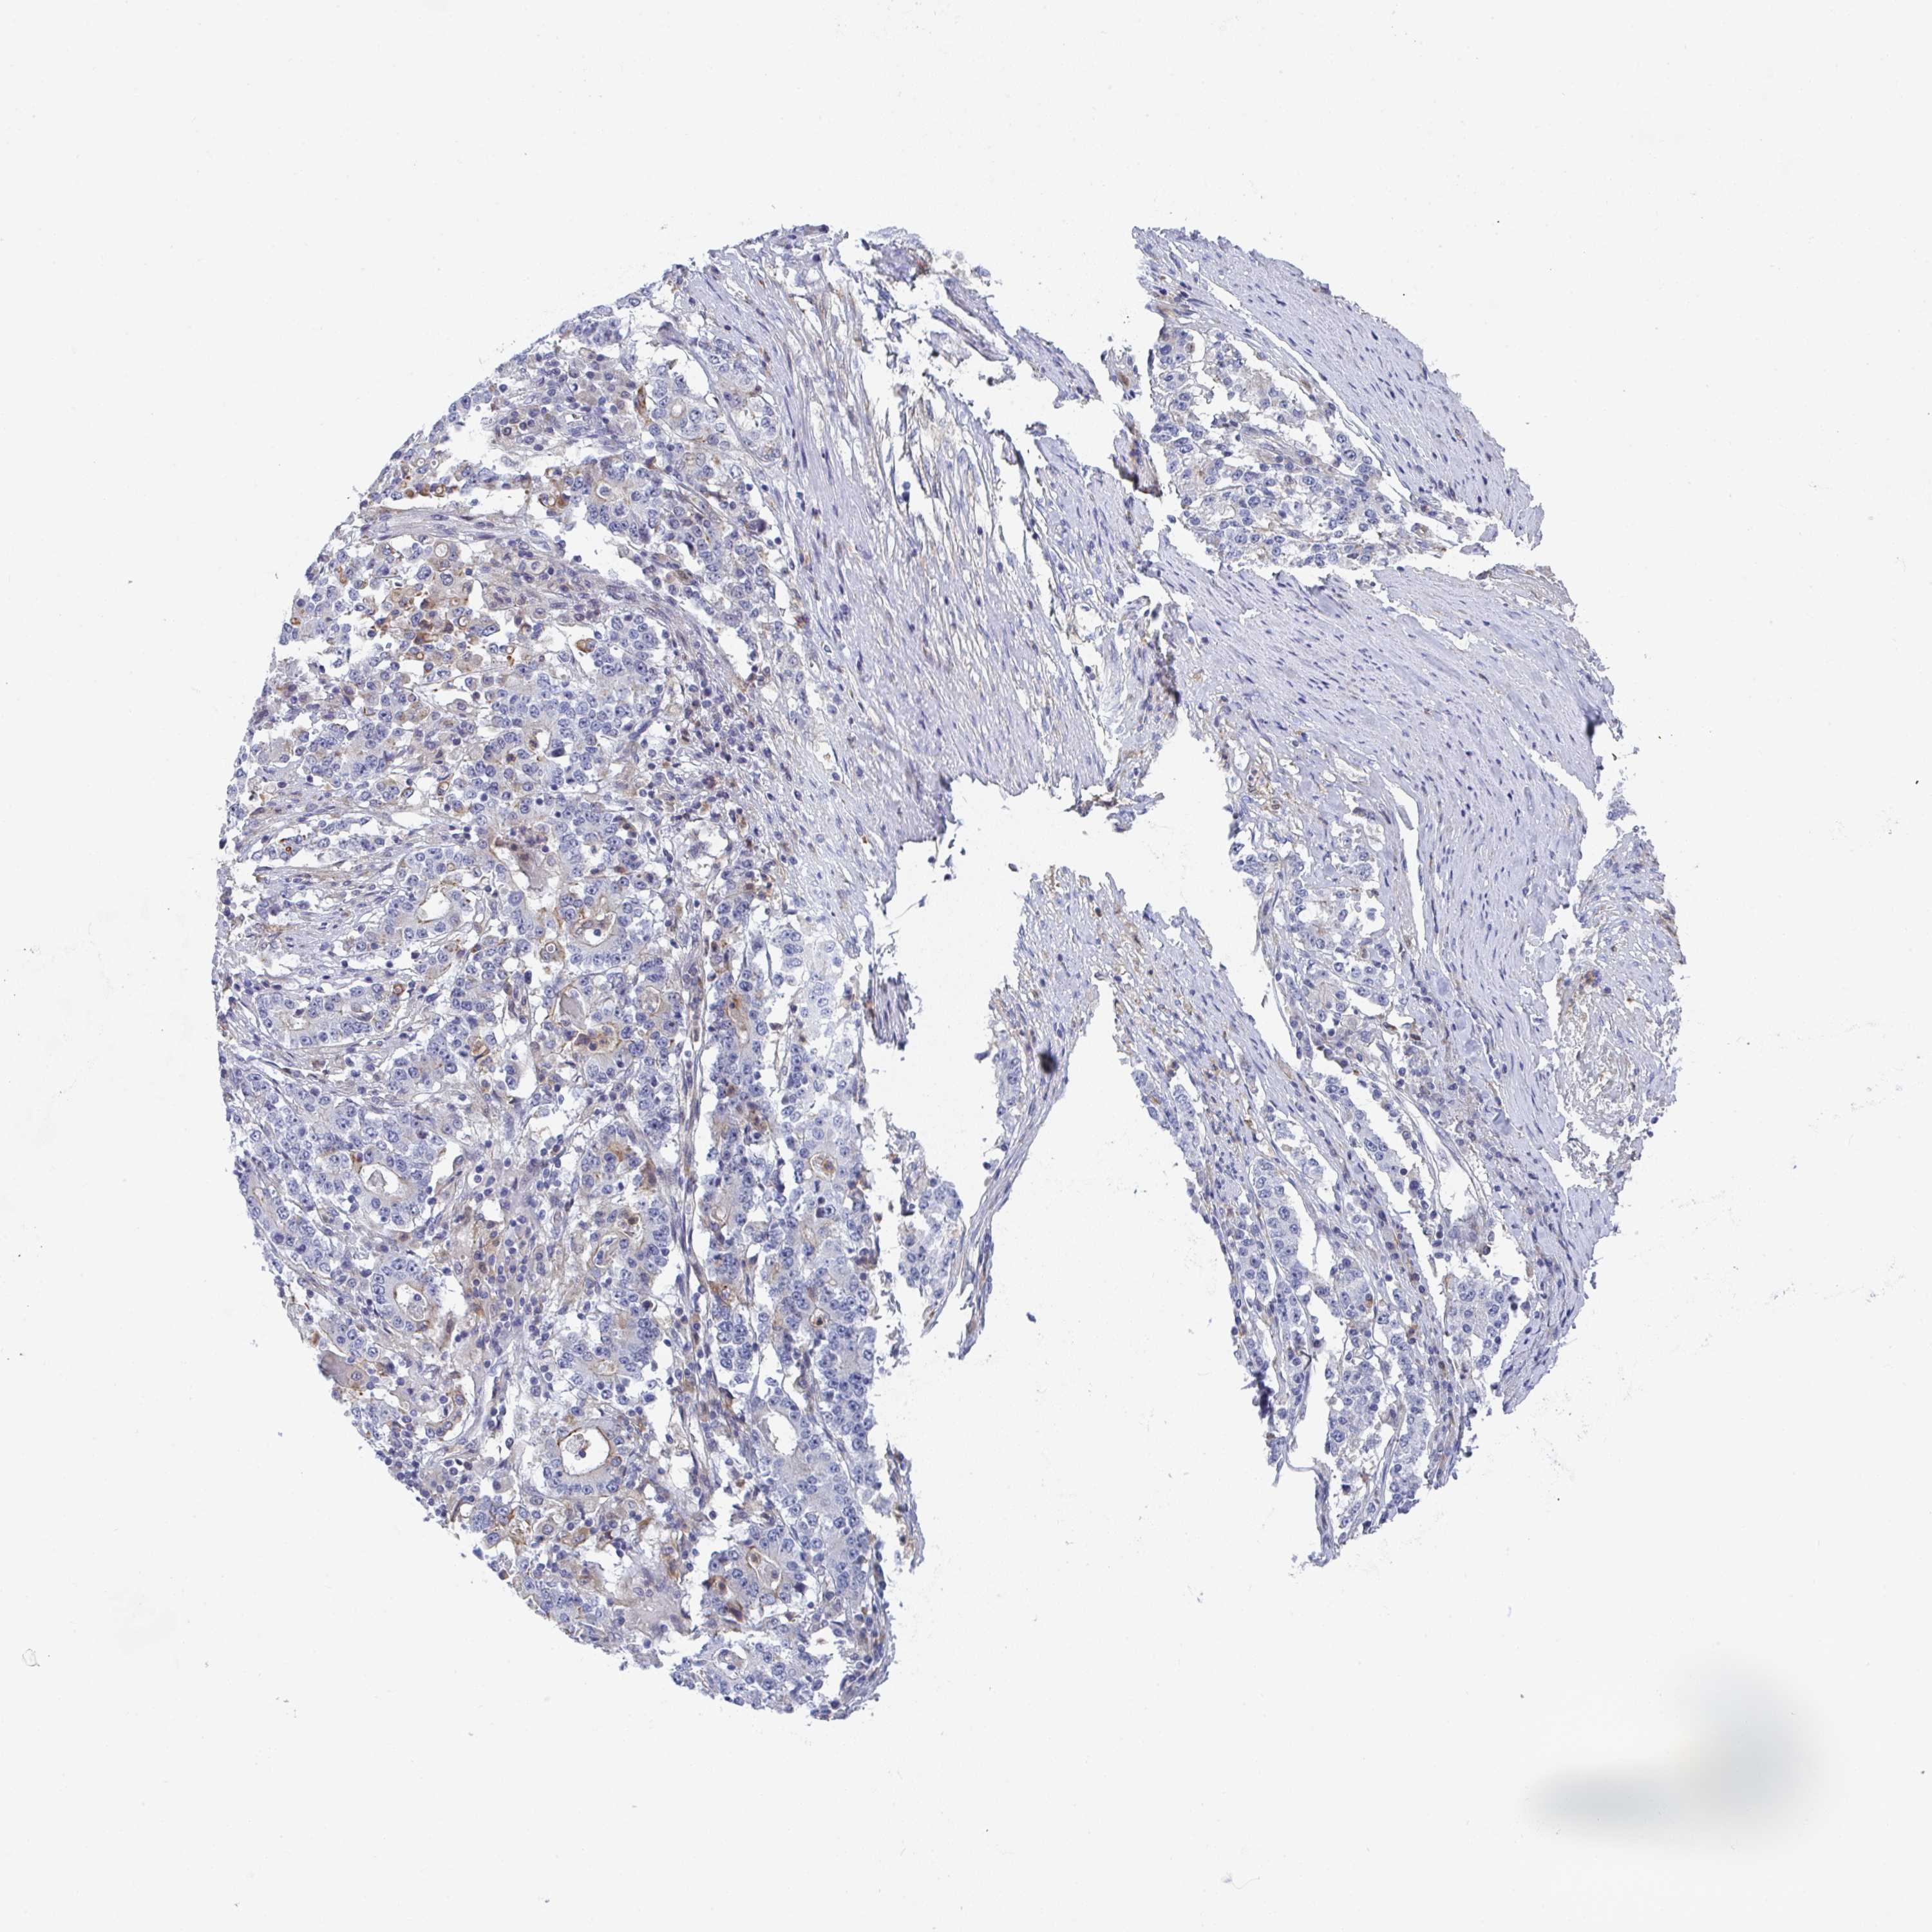

STOMACH CANCER - Protein expressioni

A mouse-over function shows sample information and annotation data. Click on an image to view it in a full screen mode. Samples can be filtered based on level of antibody staining by selecting one or several of the following categories: high, medium, low and not detected. The assay and annotation is described here.

Note that samples used for immunohistochemistry by the Human Protein Atlas do not correspond to samples in the TCGA dataset.

Antibody stainingi

Antibody staining in the annotated cell types in the current human tissue is reported as not detected, low, medium, or high, based on conventional immunohistochemistry profiling in selected tissues. This score is based on the combination of the staining intensity and fraction of stained cells.

Each image is clickable and will lead to virtual microscopy that enables deeper exploration of all samples and also displays staining intensity scores, fraction scores and subcellular localization as well as patient and tissue information for each sample.

Antibody HPA049985

Antibody HPA056560

Staining

High

Medium

Low

Not detected

Intensity

Strong

Moderate

Weak

Negative

Quantity

>75%

75%-25%

<25%

None

Location

Nuclear

Cytoplasmic/membranous

Cytoplasmic/membranous,nuclear

Adenocarcinoma, NOS

Adenocarcinoma, High grade